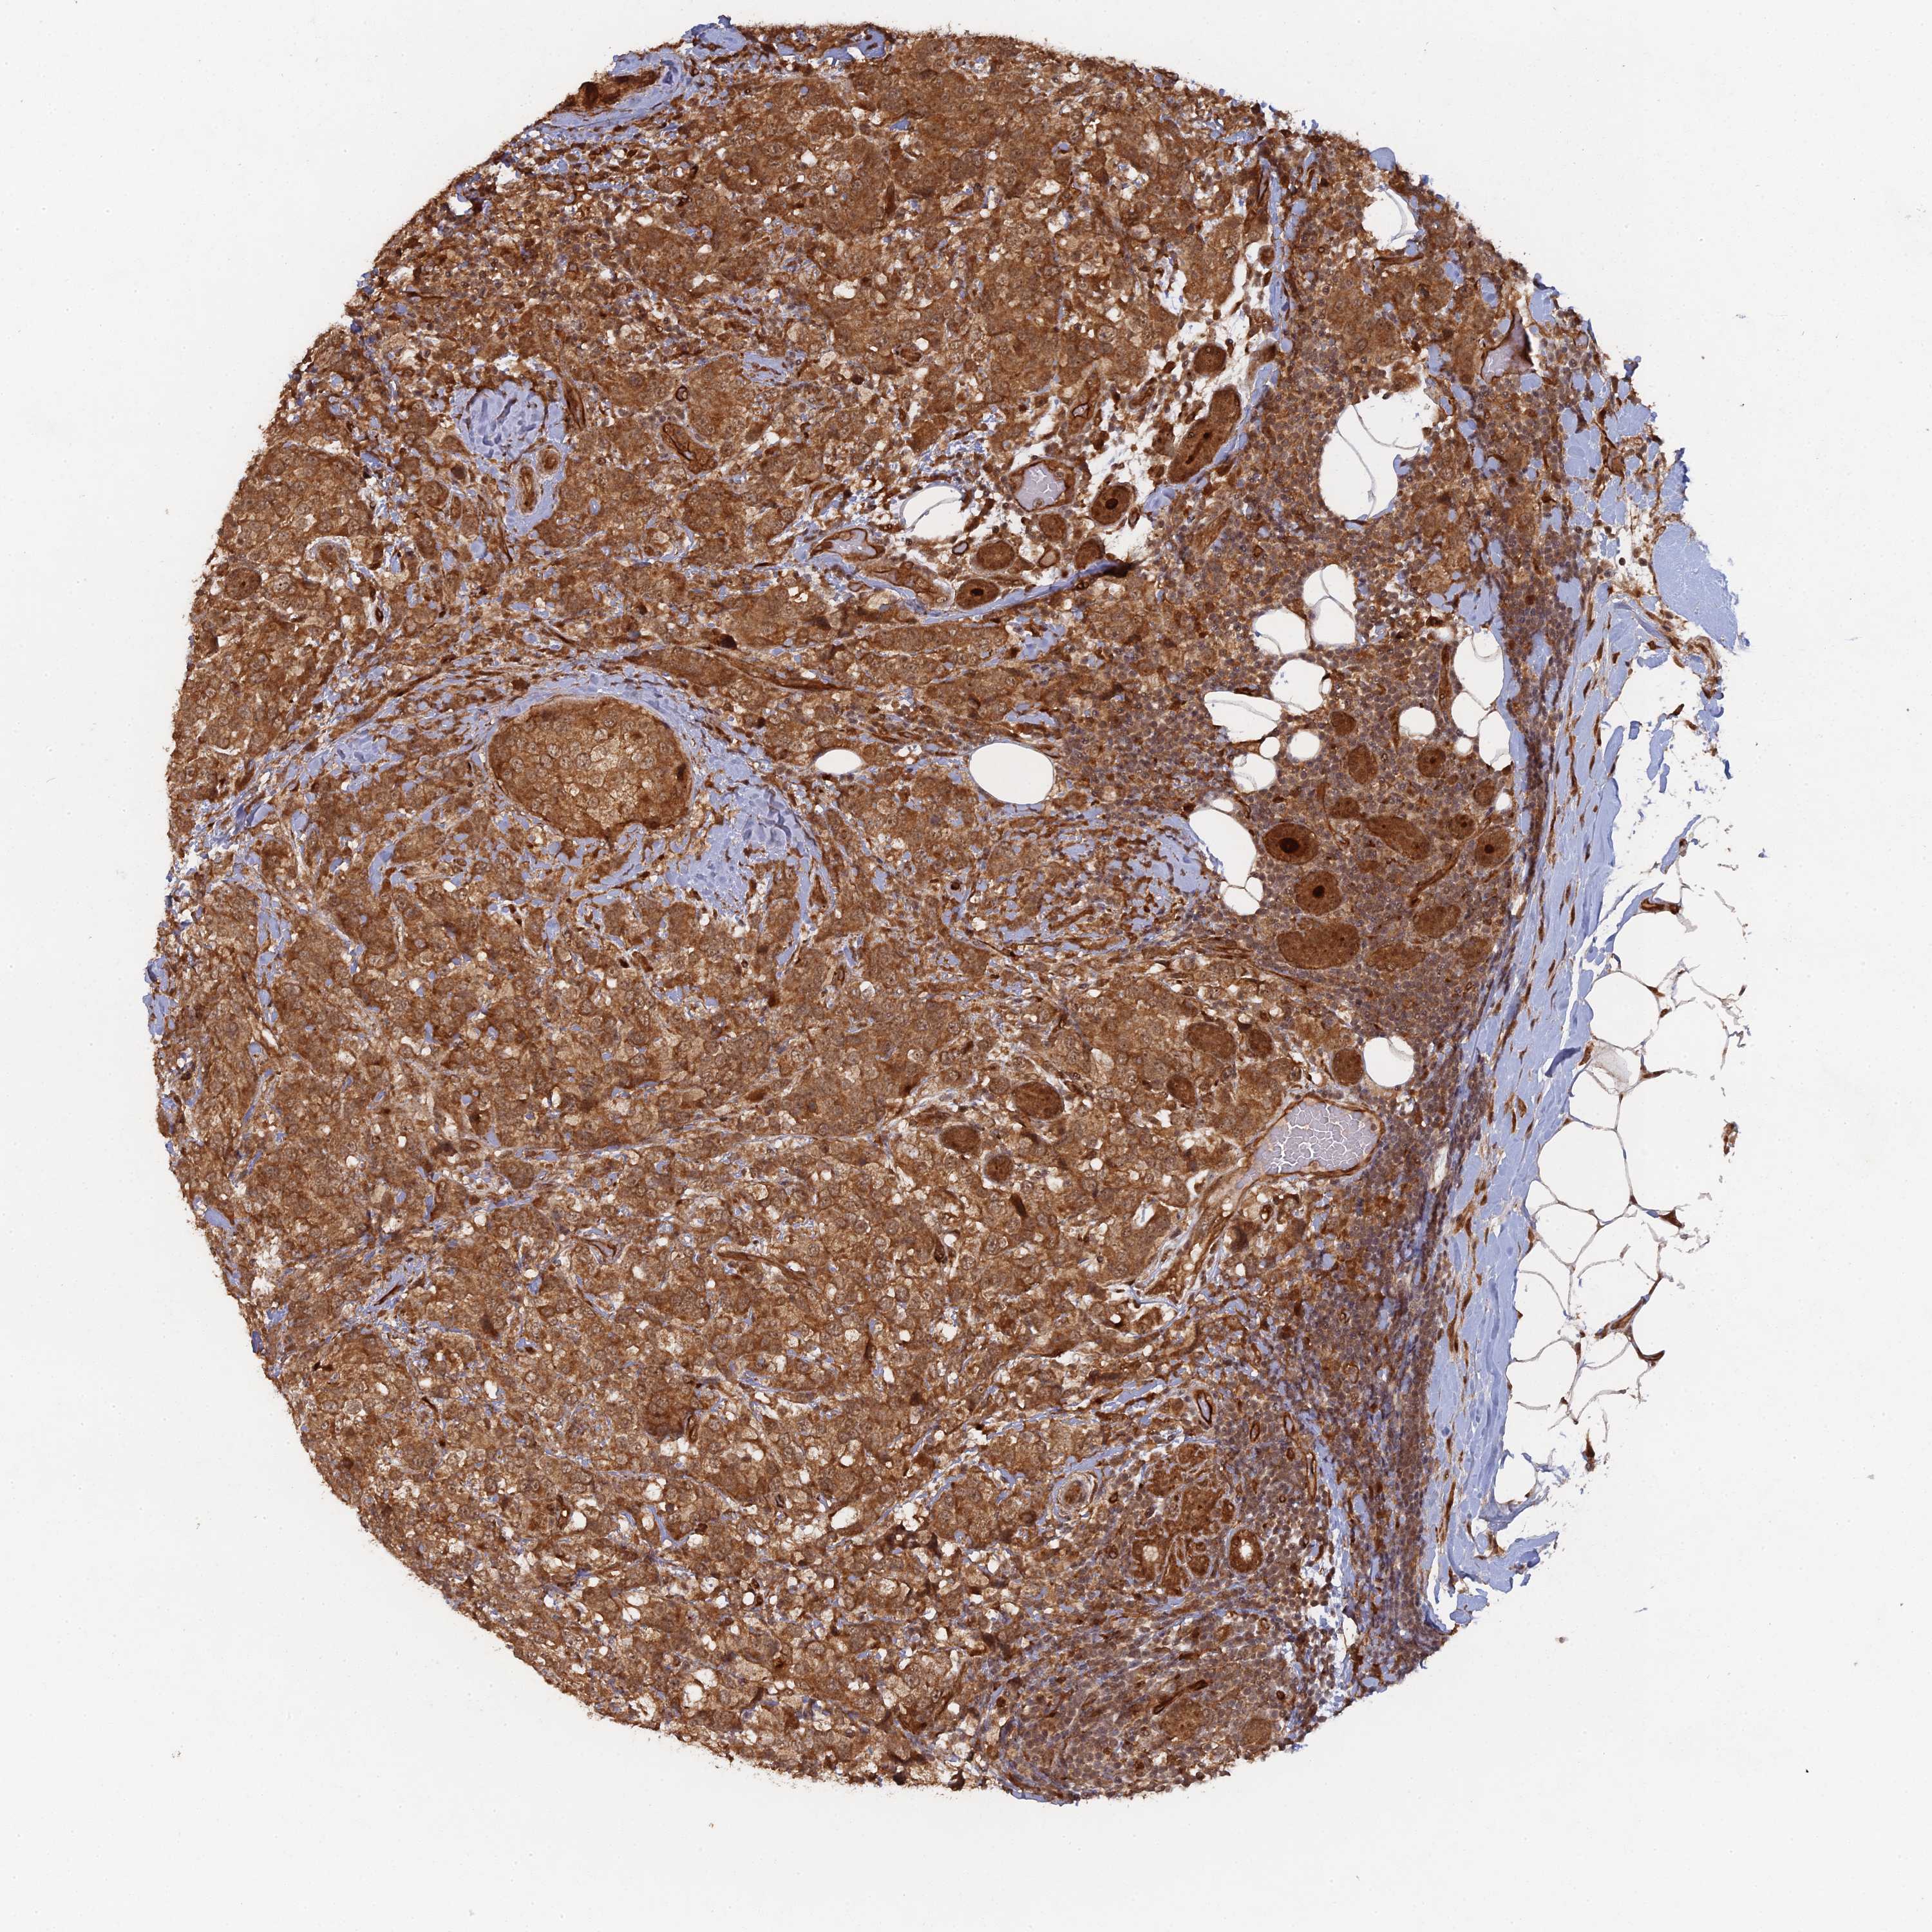

BRCA TCGA BRCA VALIDATION PROTEIN EXPRESSION

ANTIBODIES

AND

VALIDATION